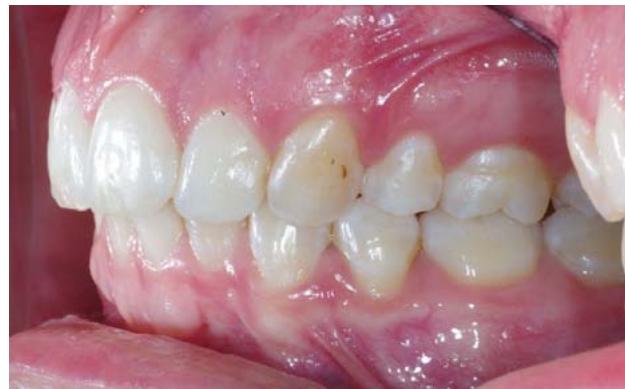

Vue du système de traction du côté droit, gauche, puis en vue occlusale.

Photos endobuccales de fin de traitement.